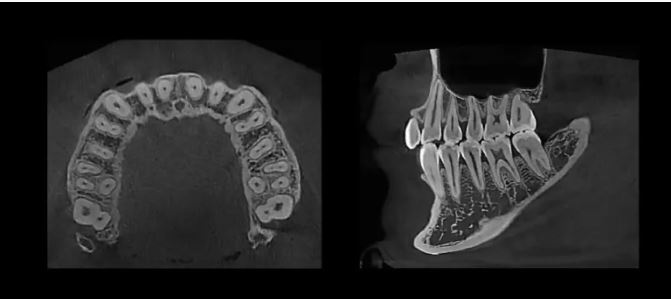

• 3D CBCT Imaging

Capture highly detailed 3D scans with a maximum FOV of 18 x 16.5 cm—ideal for full dentition, sinus evaluations, and TMJ diagnostics.

• Extraoral Bitewings

Deliver greater comfort and convenience with extraoral bitewing imaging, offering a non-invasive alternative for cavity detection and interproximal assessment.